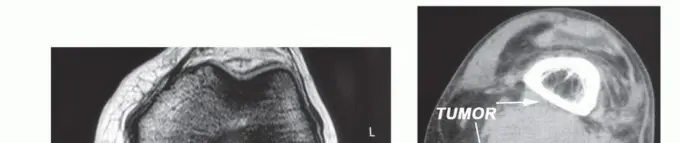

التصوير بالرنين المغناطيسي MRI

يُعد التصوير بالرنين المغناطيسي (MRI) هو الخيار الأول والأكثر تفضيلاً لتشخيص ساركوما الأنسجة الرخوة في الحفرة المأبضية. يوفر صورًا مفصلة للأنسجة الرخوة ويساعد في تحديد خصائص الورم.

- النتائج النموذجية: تظهر الساركوما عادة ككتلة أنسجة رخوة ذات مكون صلب، ولا تتصل بمفصل الركبة، وتظهر تعزيزًا مركزيًا أو عقديًا غير منتظم عند حقن مادة الجادولينيوم المتباينة.

- تقييم الورم: يُستخدم التصوير بالرنين المغناطيسي أيضًا لتقييم حجم الورم وعلاقته بالهياكل العصبية الوعائية، والمحفظة الخلفية لمفصل الركبة، والعضلات المحيطة، ولتقييم احتمال إصابة الغدد اللمفاوية الموضعية.

الأشعة السينية والتصوير المقطعي CT

- الأشعة السينية (Plain Radiography): تُجرى الأشعة السينية لاستبعاد أي غزو للورم للعظام المجاورة.

- التصوير المقطعي (Computed Tomography - CT): يُستخدم التصوير المقطعي أيضًا لتقييم مدى انتشار الورم في العظام وقد يوفر معلومات إضافية حول كثافة الورم.